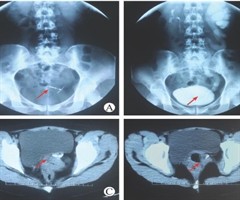

宫内节育器异位致输尿管阴道瘘的临床诊疗并文献复习

Clinical diagnosis and treatment of ureterovaginal fistula caused by intrauterine device displacement and a review of li...